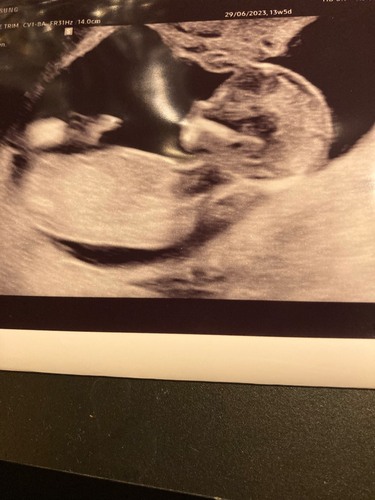

Dit is mijn 13 weken echo met 13+4 dagen. Wat denken jullie wat het wordt q ...

Als ik de skull theorie erbij pak zou ik zeggen meisje